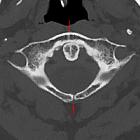

Spalt am

hinteren Atlasbogen bei einem über 70-jährigen. Korrespondierend findet sich im vorderen Bogen eine mediane Sklerosierung. Aber kein echter Split-Atlas.